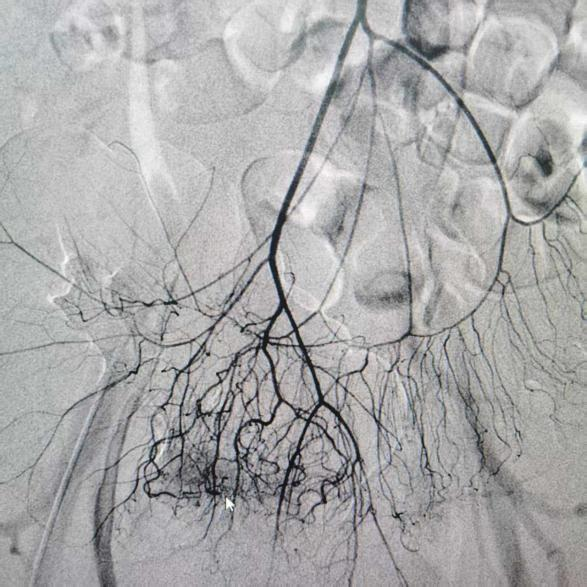

术前胃肠镜、电子直肠和结肠镜检查结果

消化内科主治医师李思刚、副主任李雷兵,在介入中心主任罗阳指导下行腹腔动脉造影。他们精细操控微导丝,携微导管至出血的血管,予以明胶海绵颗粒进行栓塞,阻断异常血流。

术后造影显示靶血管血流截断,外溢征象完全消失,达到解剖性止血目标。

术前